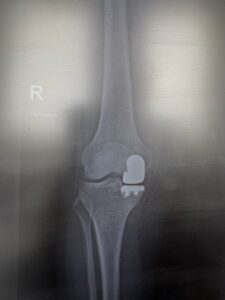

W dniu 16 stycznia 2026 r. w CSK UM w Łodzi, w Klinice Ortopedii z Pododdziałem Ortopedii Dziecięcej, został wykonany pierwszy w Europie Środkowo-Wschodniej zabieg alloplastyki połowiczej stawu kolanowego z wykorzystaniem najnowocześniejszego robota operacyjnego VELYS 🚀.

✅ Zalety zabiegu z wykorzystaniem robota VELYS w aloplastyce połowiczej stawu kolanowego:

- 🦴 mniejsza ingerencja w staw,

- 🎯 znacznie większa precyzja operacyjna,

- ⚡ szybsza rehabilitacja,

- 💪 krótszy czas powrotu do sprawności i zdrowia.

Alloplastyka połowicza stawu kolanowego